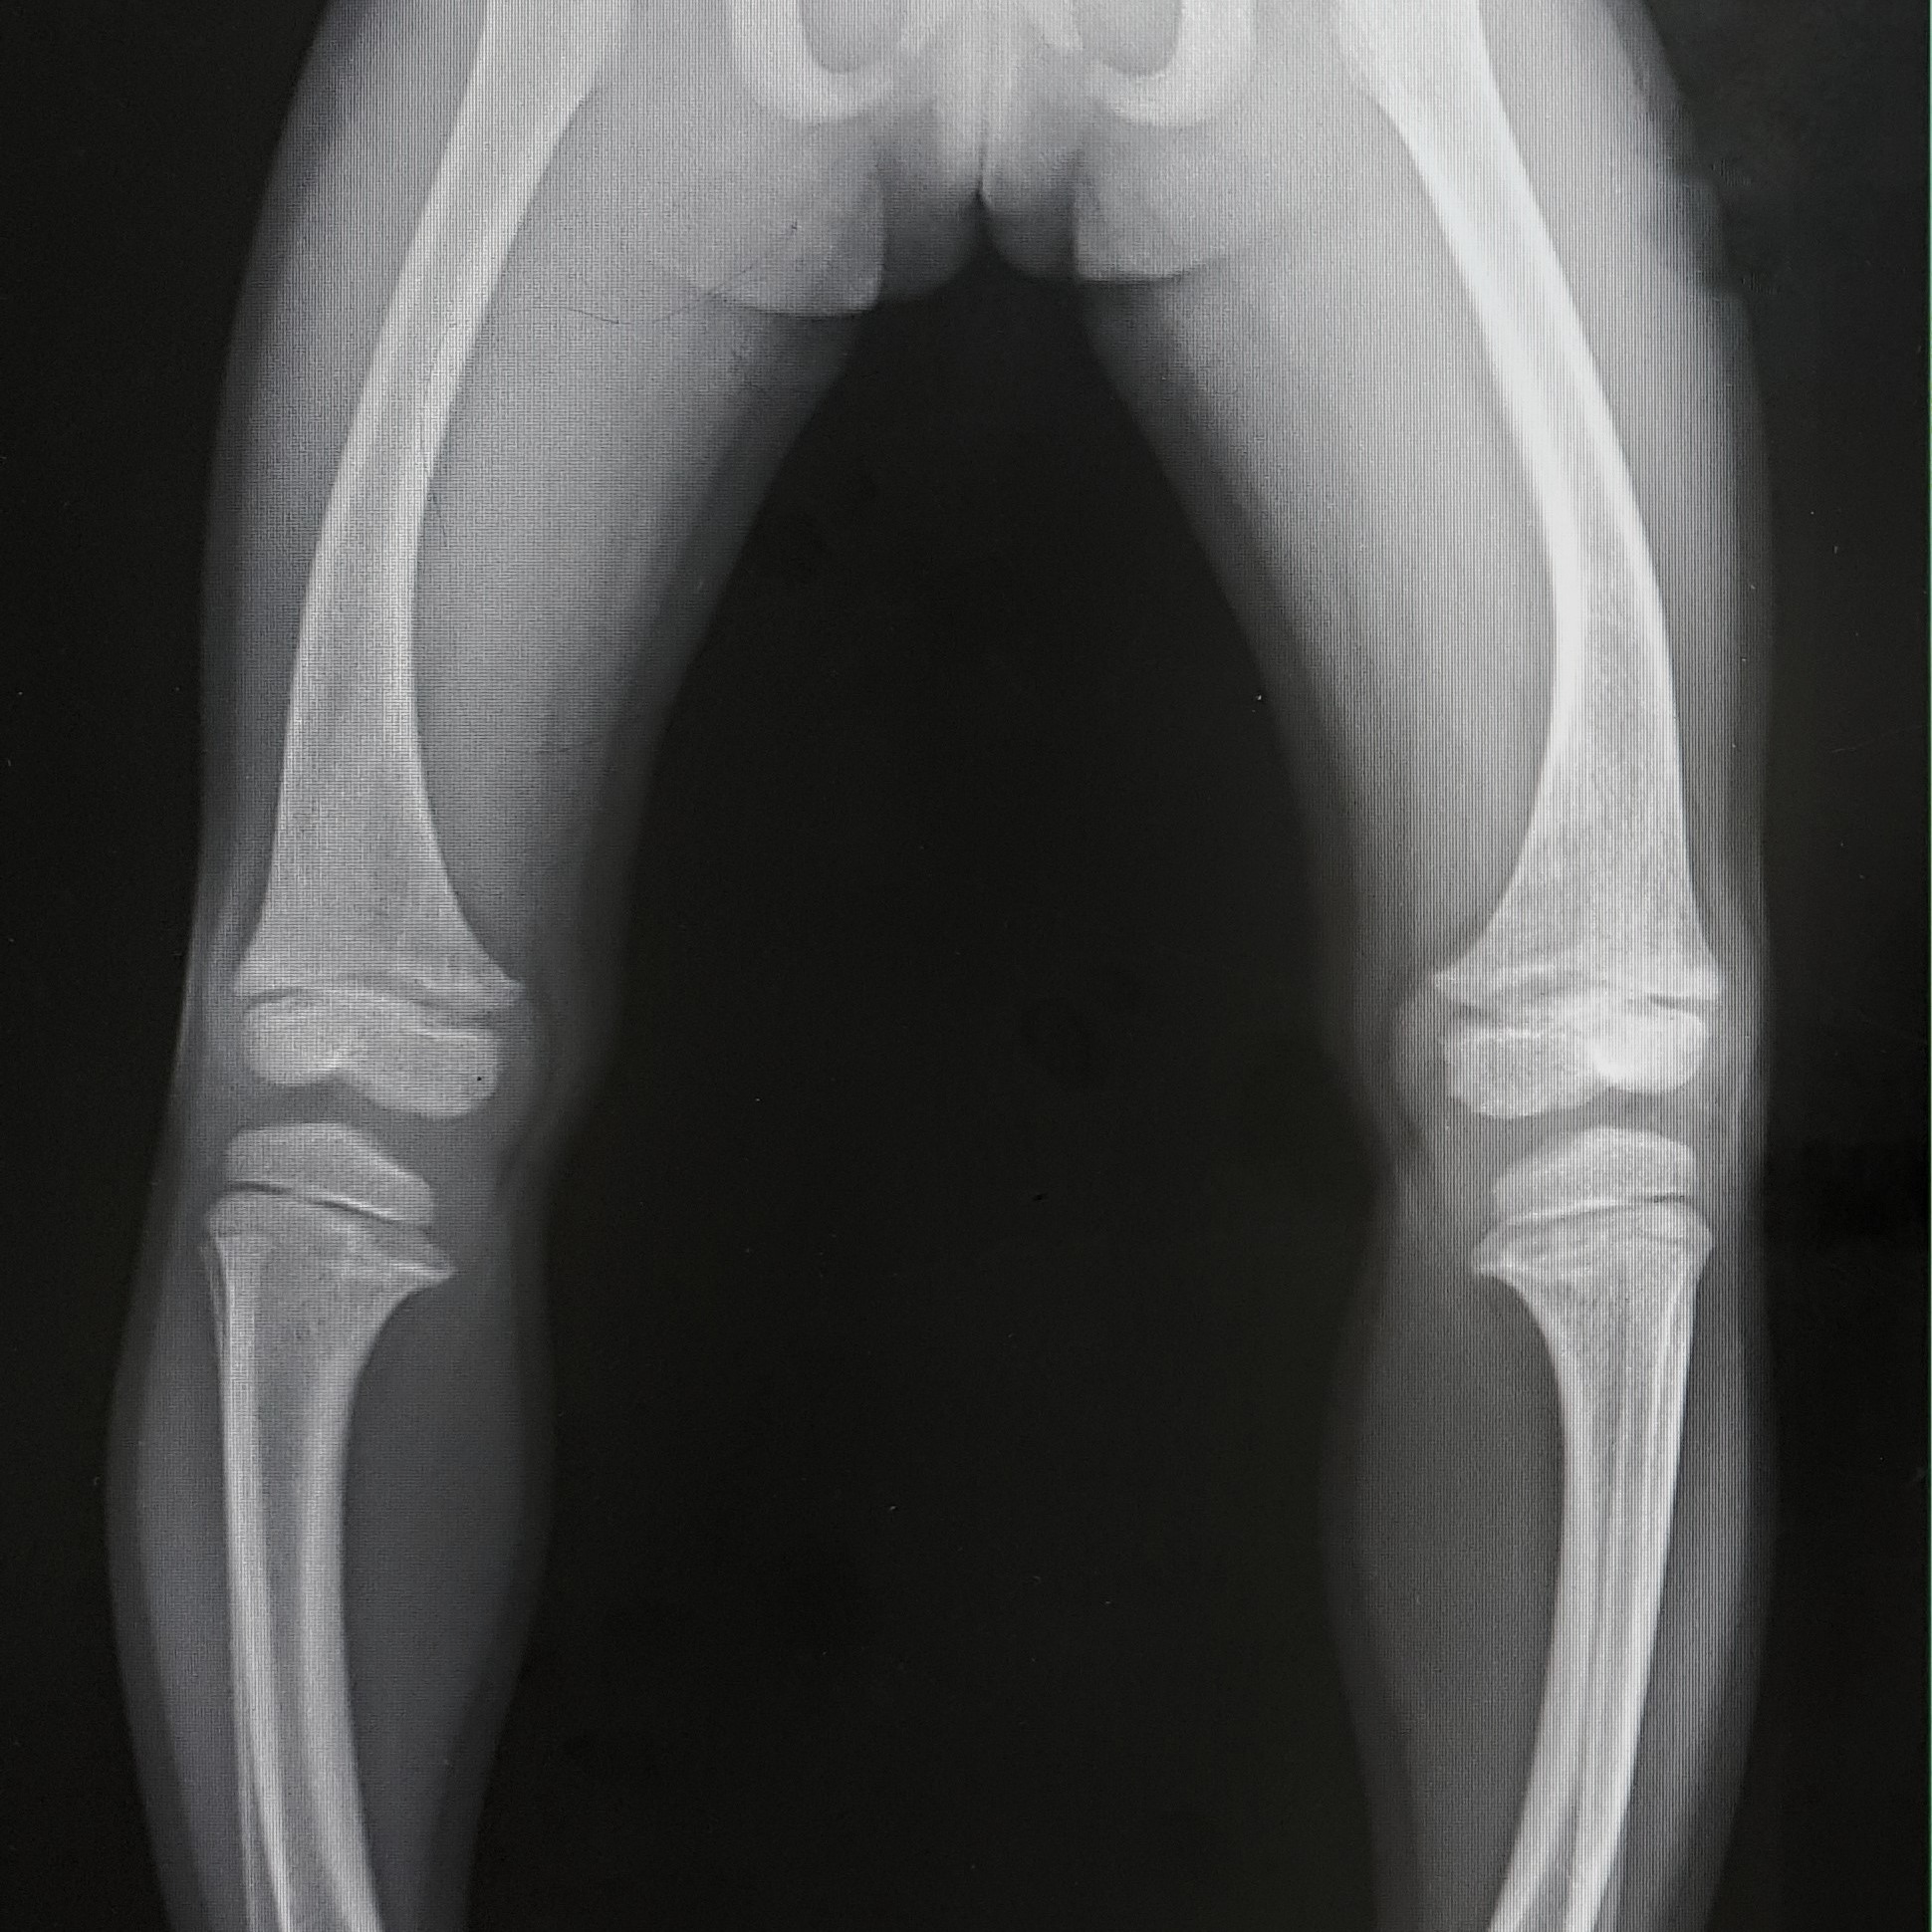

Tale patologia è tipicamente riscontrabile nei pazienti di età adulta, se presente, invece, nei bambini, è chiamata rachitismo. A differenza dell’osteoporosi, che causa principalmente una minore massa minerale ossea, l’osteomalacia è specificatamente caratterizzata da un’alterata mineralizzazione.

• incurvamento e deformità delle ossa delle gambe;